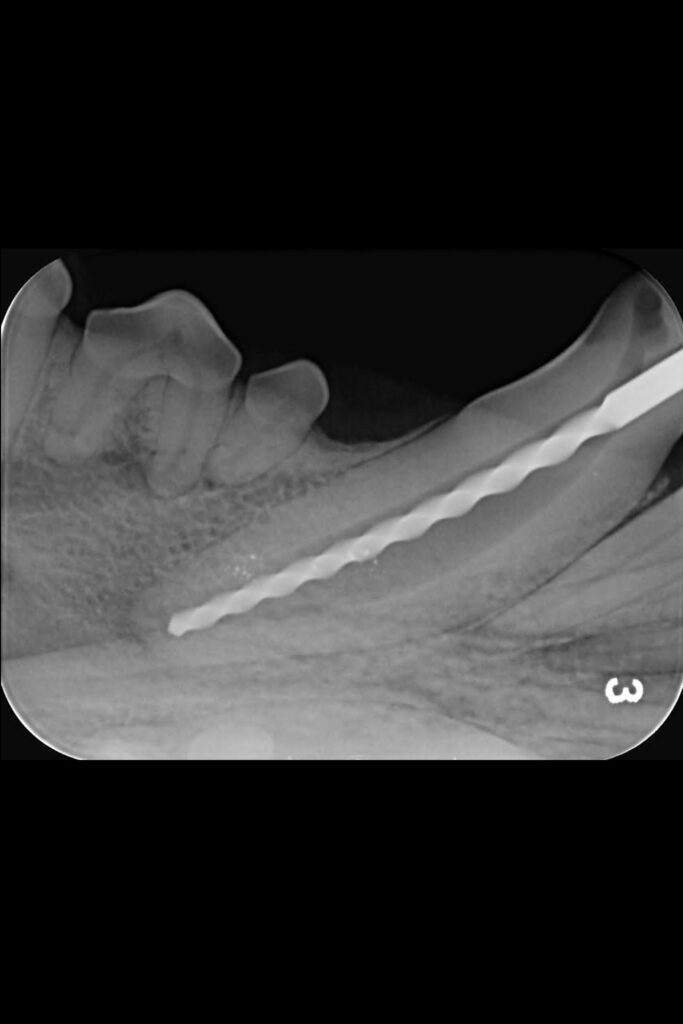

Initial radiographs were taken on our intraoral dental-specific X-ray unit to evaluate the dense tooth and bone structure. This revealed what was happening within the tooth and beneath the gumline – all the areas that cannot be seen with a visual examination. These showed not only the crown fracture but also a wide pulp chamber, which required root canal treatment.

A key part of this treatment involves inserting increasing file sizes into the tooth to reach the pulp to remove any infected or necrosed tissue. X-ray images are then again taken at various points throughout the procedure to check file size and position.